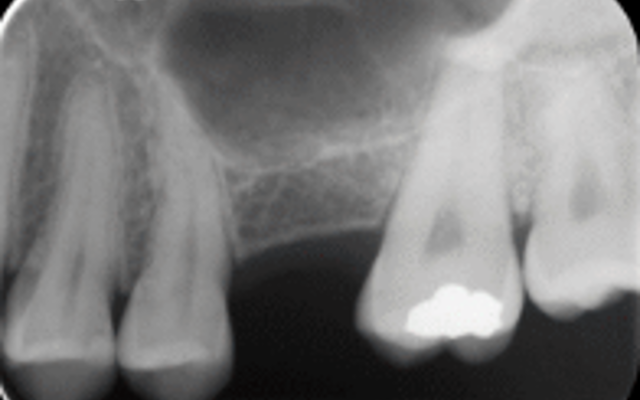

Bone regeneration around dental implants is achieved by grafting bone. Most commonly bone grafting is required when a patient does not have enough healthy natural bone at the dental implant site to support a dental implant. (Figures 15 A, B & C).

This deficiency of natural bone can be caused by infection (often caused by a fractured tooth root, gum disease or root canal complications), or it can occur because of a slow loss of bone that happens after a tooth was extracted more than a couple of months or longer beforehand.